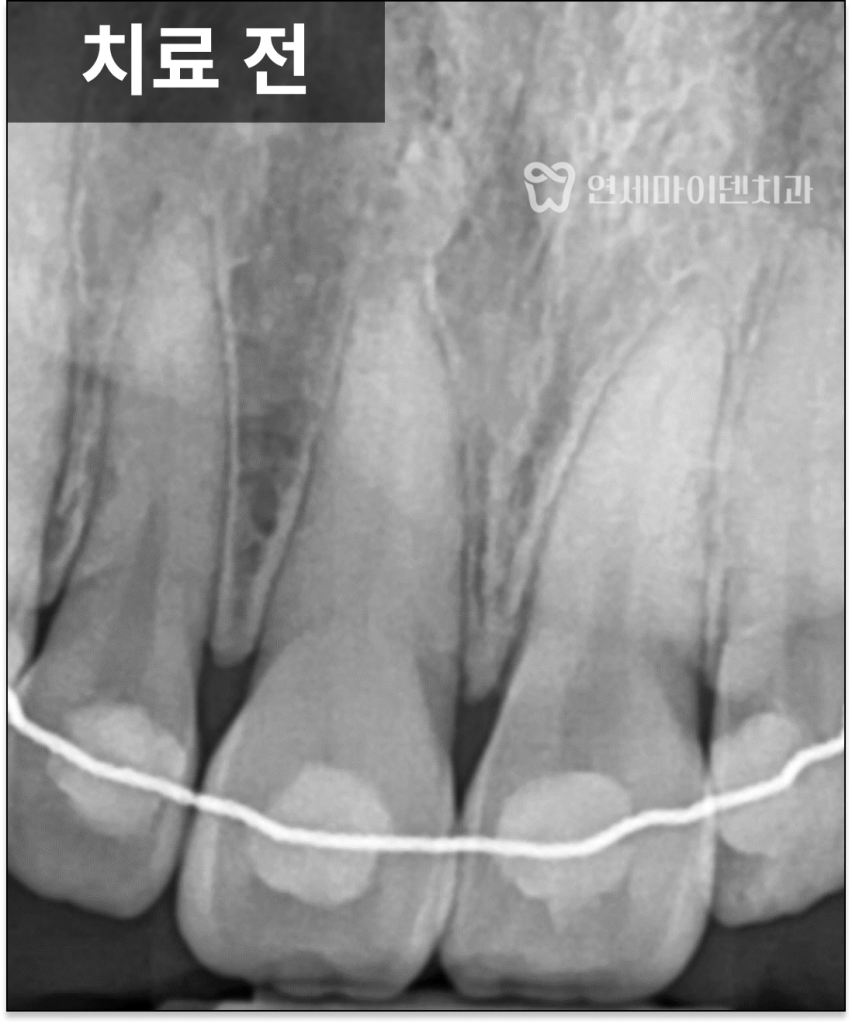

이번 케이스에서는

냉검사와 전기 검사 모두에서

반응이 나타나지 않아

신경이 이미 괴사된 상태로 판단했습니다.

실제로 치료 과정에서 확인해보니

치수는 이미 괴사된 상태였습니다.